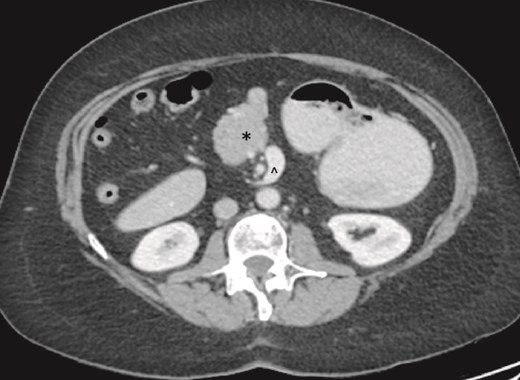

On examination, the abdomen was soft but mildly distended. Bowel sounds were heard, and the epigastrium was mildly tender. Standard bloodwork was normal. Review of an abdominal computerized tomography (CT) scan from 4 years prior showed congenital malrotation of the bowel, with the small bowel to the left of the midline and colon entirely to the right (Fig. 1). There was partial agenesis of the dorsal pancreas (Fig. 2), azygous continuation of the inferior vena cava (IVC), a retroaortic and retrocrural left renal vein, and an unremarkable spleen alongside some splenules. The PV traversed anterior to the first part of the duodenum (Fig. 3). There was relative narrowing of the distal stomach and the duodenum was nondilated.

Terminal ileum (*) seen entering cecum with completely right-sided colon and left-sided small bowel visible. PDPV also seen (^) causing partial duodenal obstruction.